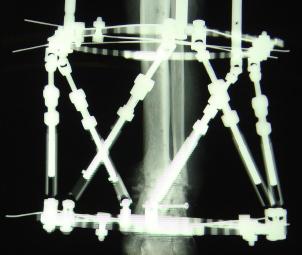

Postoperative (13th) images of left ankle

The image(s) displayed here were created following Liam's 13th surgery which was performed by Dr. Saunders. After a few hiccups getting

the surgery scheduled, Liam spent most of the September 13th afternoon in his 13th surgery. ;-) The surgery lasted about 5 hours and according

to the doctor, it was a good surgery. The 1st photo shows the new frame bracing that holds Liam's ankle together. The next series of photos show

various angles of the ankle and the rods that go from the frame into and through the left ankle. There was some concern that the swelling would

burst and allow for infection. Looks like we are now past that concern. Liam is still on antibiotics to ward of potential infection. The flesh

images show how the skin reacts to having the leg adjusted by the brace. The doctor has had to cut the skin to allow the rods to move freely.